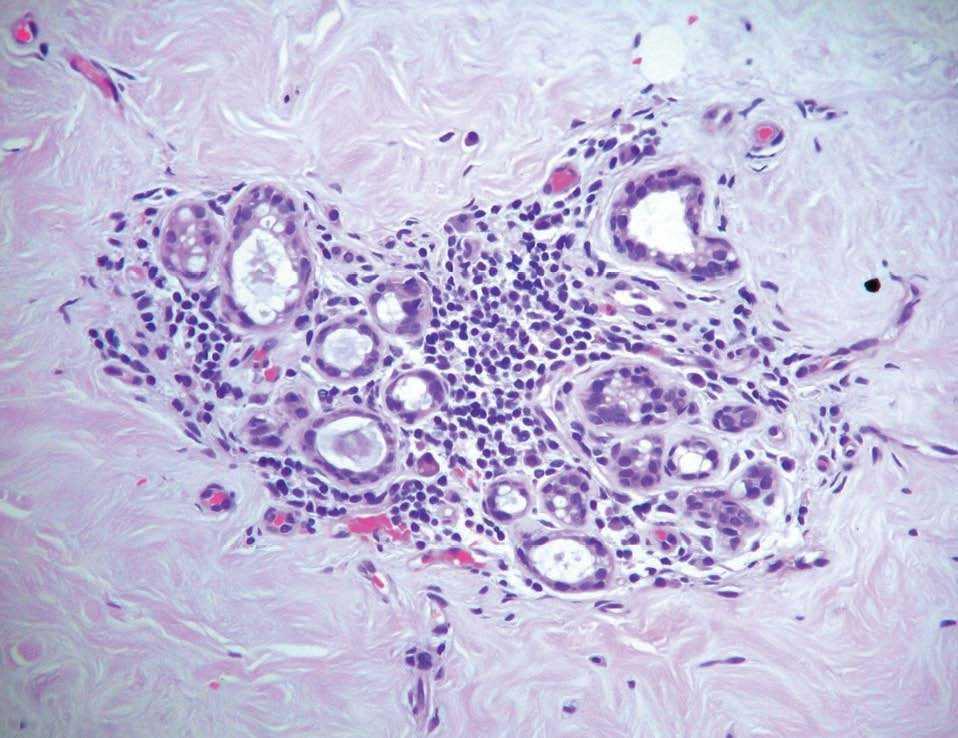

Histológicamente, se trata de una fibrosis densa de la estroma y una infiltración linfocitaria (principalmente de linfocitos B) alrededor de los vasos sanguíneos, ductus y lóbulos mamarios (figs. 1 y 2).

Figura 1. Mastopatía diabética.

Figura 2. Mastopatía diabética.